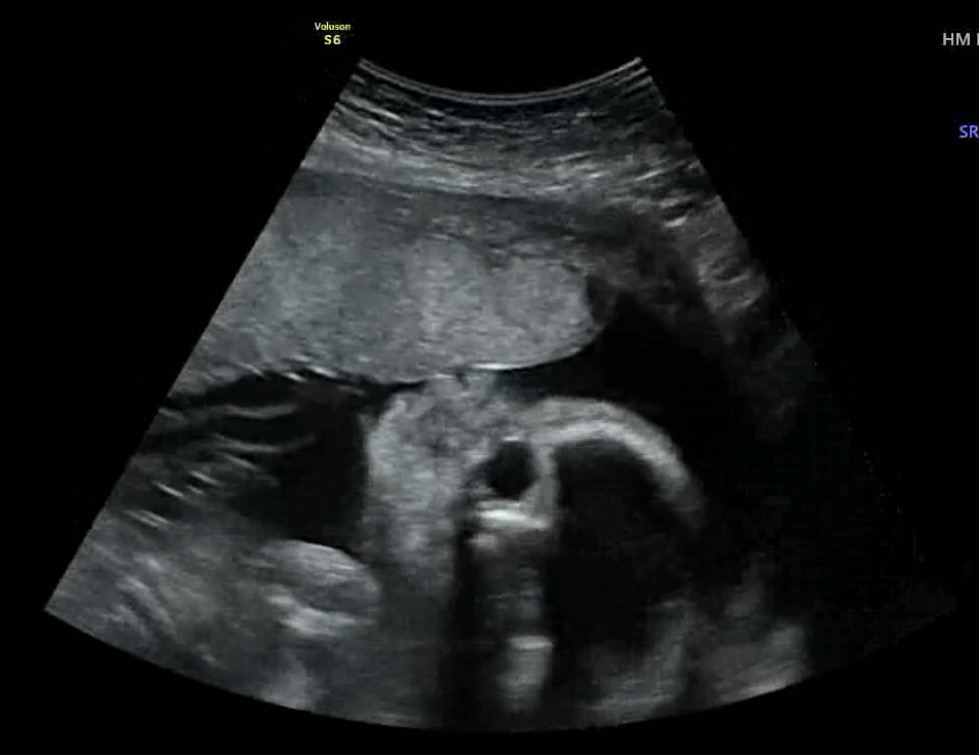

오늘 공포의 임당검사를 하고 왔습니다. ㅠㅠ 오전에 임당검사가 있어서 검사 2시간전에 미리 아침식사를 하고 갔습니다~ 의사쌤이 먹고 오는게 혈당이 안튄다고 하더라구요. ㅎㅎ 밥은 적게 콩나물, 김치볶음, 두부, 시금치 이렇게 먹고 혈당검사 했더니 수치가 96으로 무사 통과했답니다..🤍 그런데 철분수치는 10.7이 나와서 철분제를 따로 챙겨 먹어라고 하네요 ㅠㅠ 혹시 비리지 않고, 변비생기지 않는 철분제 알고 계신다면 추천좀 해주세요! (아 촘파 사진은 오늘자 똥별이 사진입니당🤍 태반에 뽀뽀하고 있는 모습이 귀엽죠?🥰)